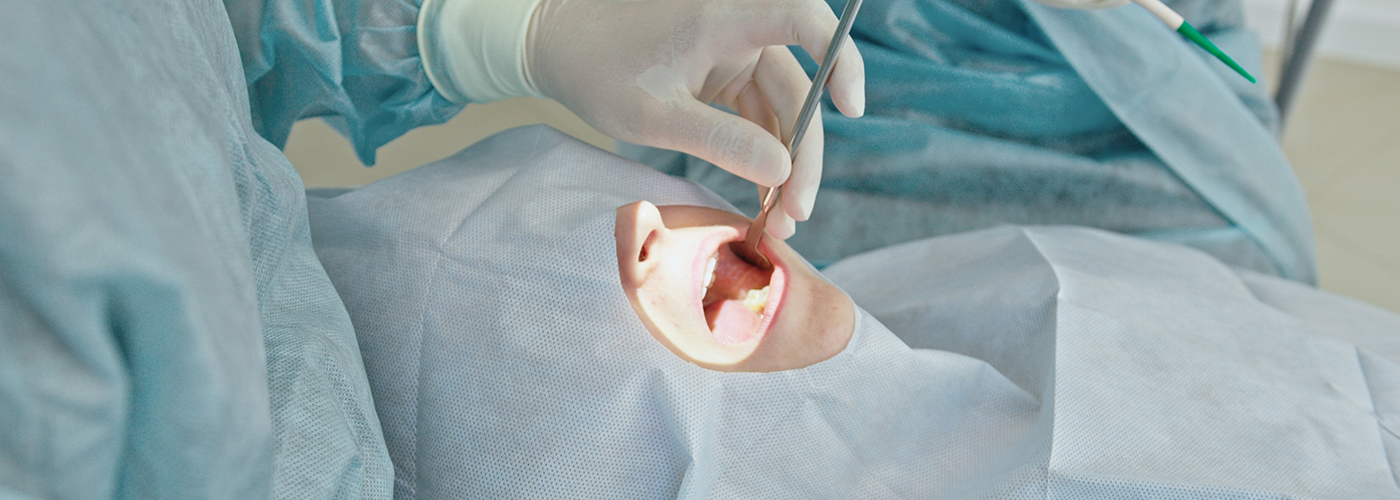

잇몸에 고름이 차 있다면 배농이 필요하고, 잇몸을 절개해서 염증조직을 제거하거나 치은이나 뼈를 이식하는 수술을 시행하기도 합니다.